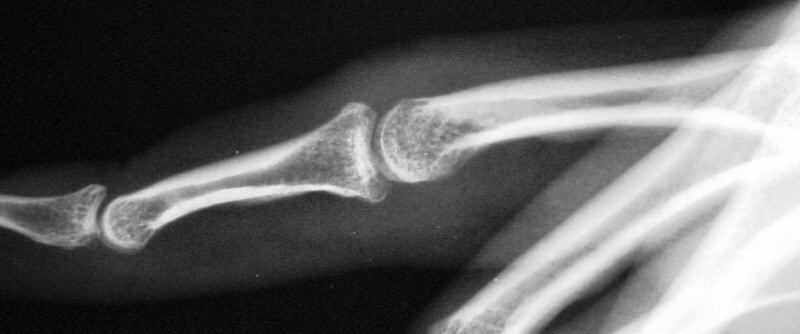

Case 1. 14 year old boy with radial prominence and ulnar deviation of the middle finger proximal interphalangeal joint. Painless, no history of trauma.

Radiographs showing well circumscribed calcification at the  proximal phalanx collateral ligament origin, 10 degrees of lateral angulation.